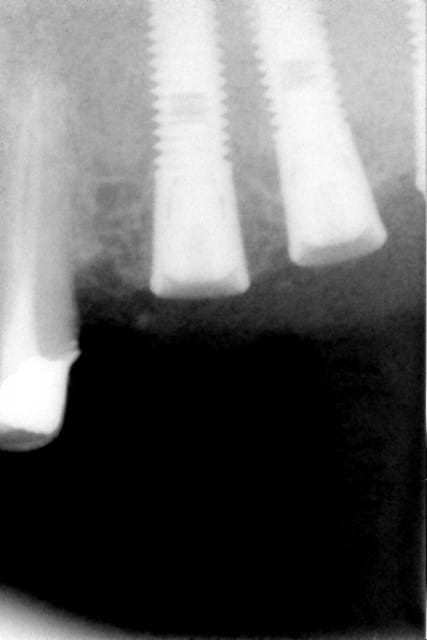

Radio1 nedqqo - Eugenol

Radio2 jxft6m - Eugenol

c'est quoi cette image radio au niveau de 46??

Je change un peu de sujet, mais sur la pano ; avez vous remarqué l'image peu banale au niveau de l'ancienne 38 ? On dirait presque un canal dentaire dédoublé.

Quelqu'un a un avis sur cette image ?

tu as la meme image a gauche qu'a droite, il s'agit peut etre simplement d'un manque de contraste radio...le canal dentaire est dessous...